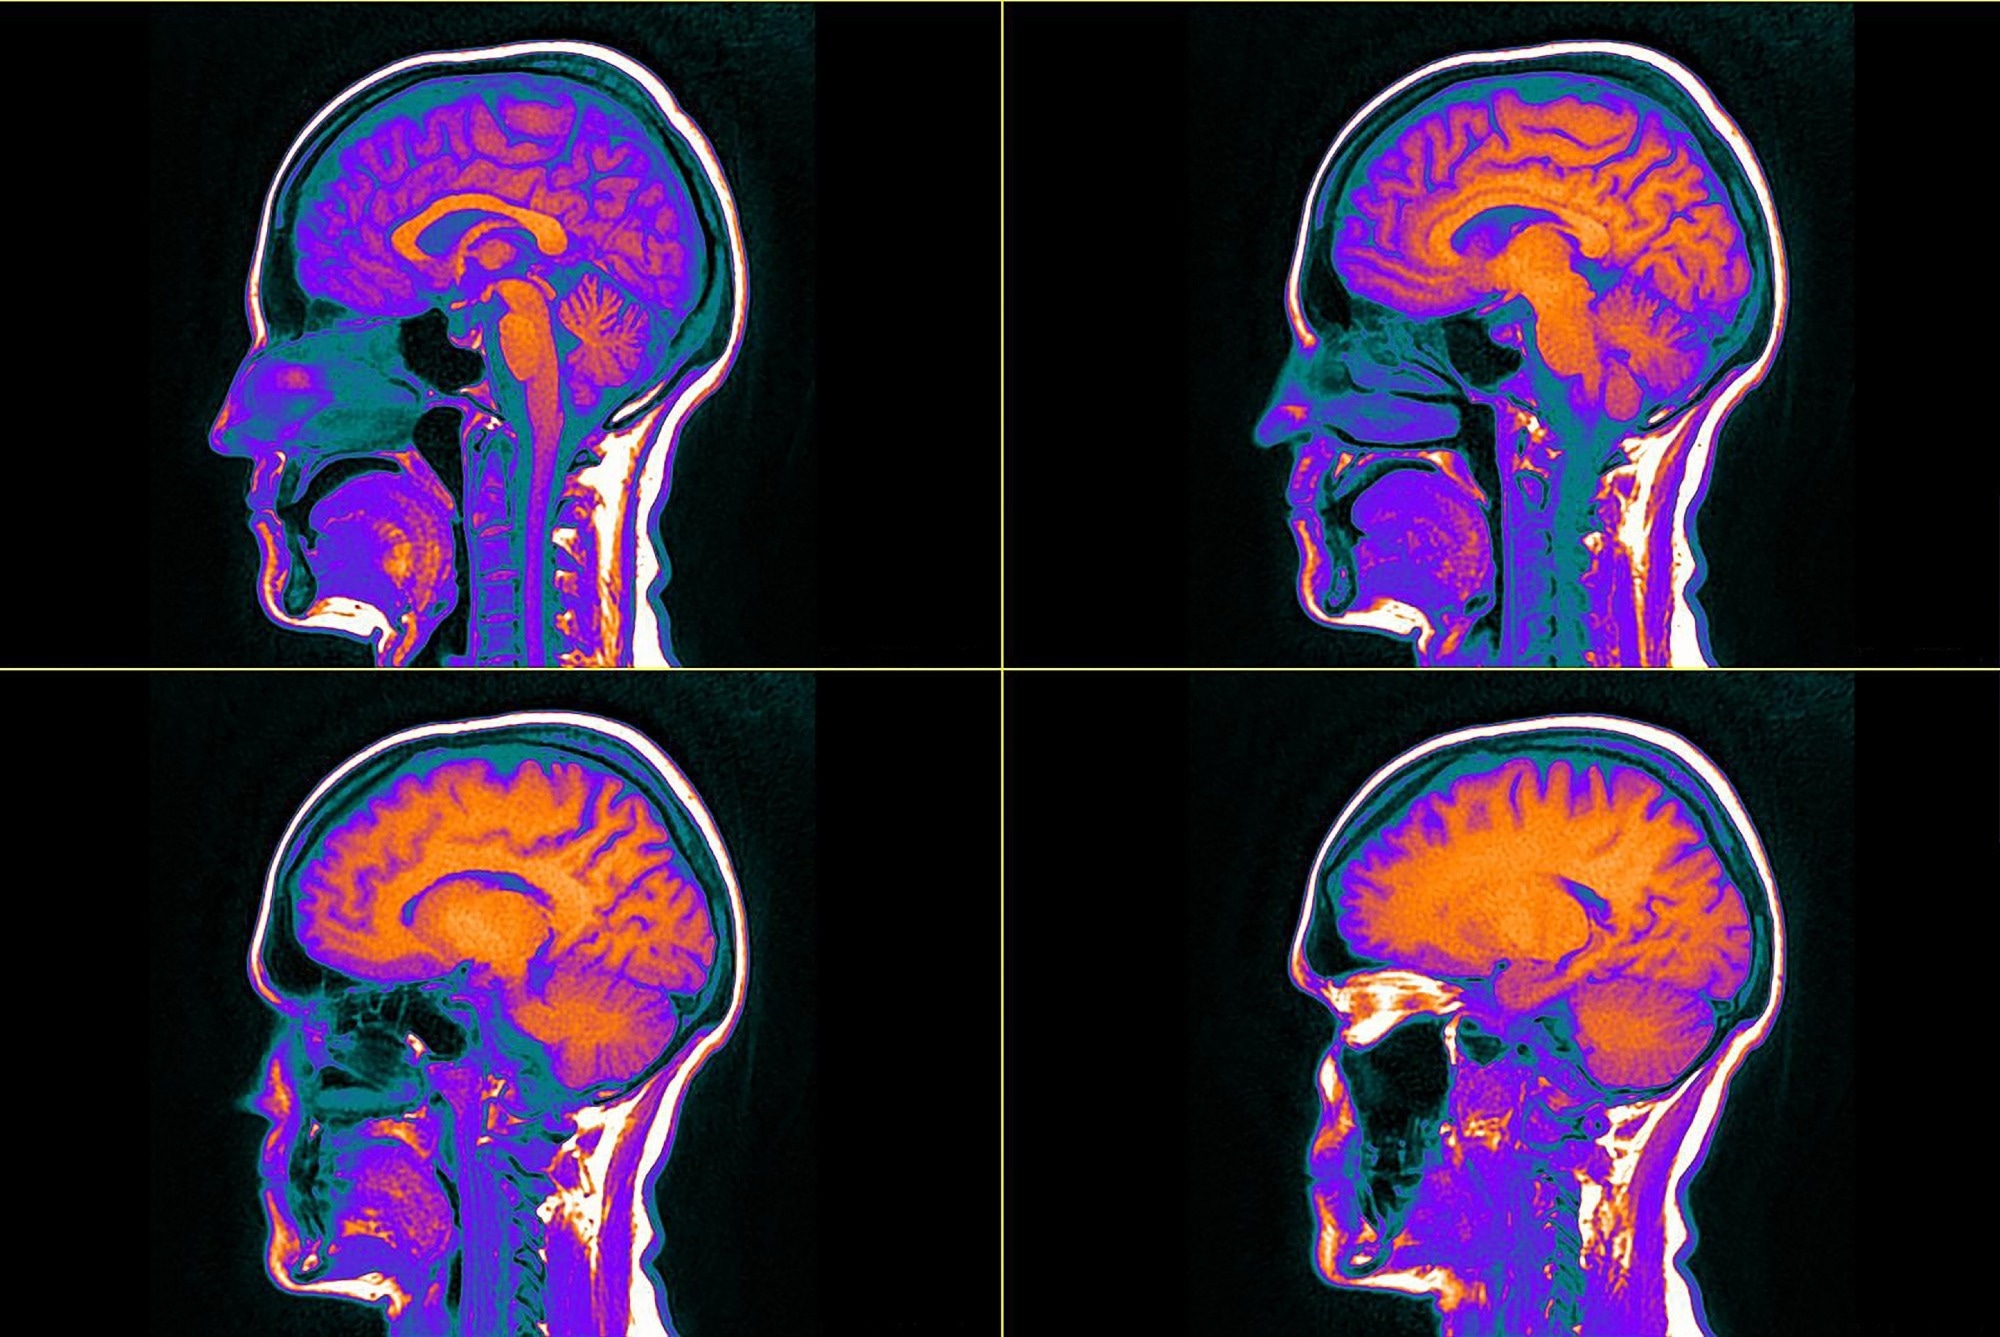

Study: Nicotine-related beliefs induce dose-dependent responses in the human brain. Image Credit: dore art / Shutterstock.com

All study participants underwent functional magnetic resonance imaging (fMRI) and completed a decision-making task known to involve nicotine-affected brain networks. Study participants were also assigned a value-based decision-making assignment, during which they had to place positive and negative bets.